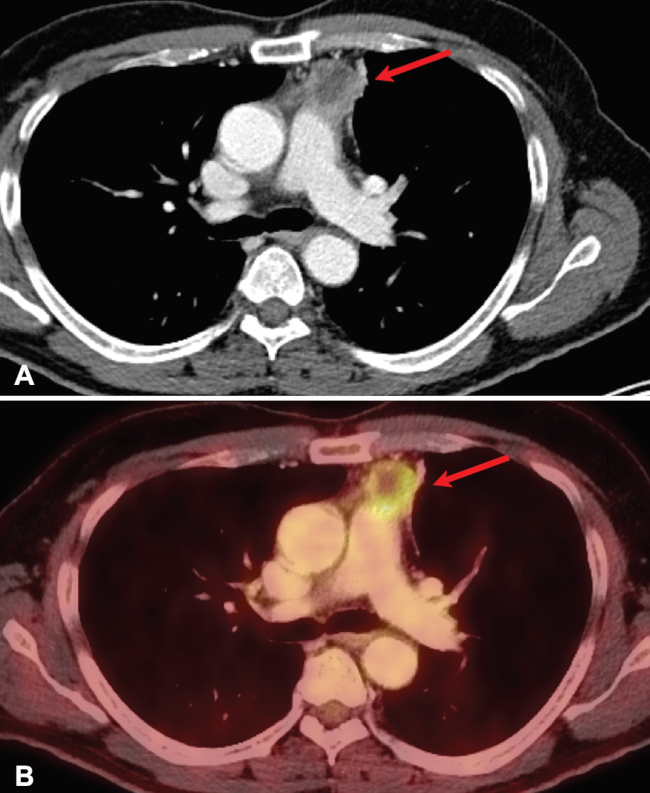

El carcinoma tímico puede ser difícil de distinguir mediante imágenes de un timoma localmente avanzado, pero el carcinoma tímico tiende a ser más agresivo, con rápida invasión de estructuras adyacentes. El carcinoma tímico por lo general carece de cápsula y las adenopatías y metástasis a distancia orientan a ese diagnóstico. Generalmente, se presentan en TC como masas multilobuladas, heterogéneas con áreas de necrosis y calcificación. Su captación es alta, típicamente con un SUVmáx mayor a 7 (►Fig. 6).6